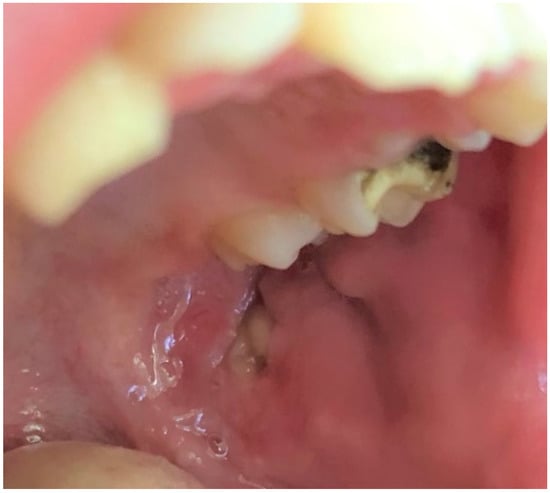

The third most frequently observed mucosal lesion in studied population was Morsicatio buccarum (MB). As pictured in Figure 5, this condition is characterized by a rough, whitish, shredded oral mucosa and develops due to the parafunctional, habitual biting/chewing of the buccal mucosa. The overall frequency of its occurrence was 9.1%, similar to what was observed among 0–12 y/o Brazilian children (8.4%) [27]. Jimenez et al. also found high incidence of this disorder, amounting 15.87%, among Venezuelan children aged 2–17 [28]. In many other researches, Morsicatio buccarum was diagnosed as one of the most common OMLs in children, but with varying incidence [2,3,17]. Nevertheless, it should be underlined that in many cases MB was included in the group of trauma-associated lesions (along with erosions, ulcers, etc. caused due to injuries or dental and orthodontic treatment), so it is difficult to directly compare the results [1,9,10,20], however the incidence rate of such compiled diagnoses was also very high in each study group. In our investigation, MB was the second most frequent diagnosis among boys and the 5th most commonly recognized in females, but there was no significant difference between the genders. This correlation was also observed in the work of Jimenez-Palacios et al. [28]. The number of MB cases was significantly increasing with age (p = 0.04), which was also observed by other researchers [2,9,10,27,28]. This observation can be explained that MB is considered as a parafunctional activity that develops in response to higher psychological overload, higher stress and anxiety, especially the one related to school and studying stress, which intensifies with the age of pupils [9,29,30,31].

Figure 5.

Morsicatio buccarum on the left buccal mucosa of a teenage boy. In this patient, the lesion was observed bilaterally in an atypical location in the midpart of the buccal mucosa along with occlusal line. The mucosa is white, thickened, shredded, and combined with zones of the erythema and erosion.